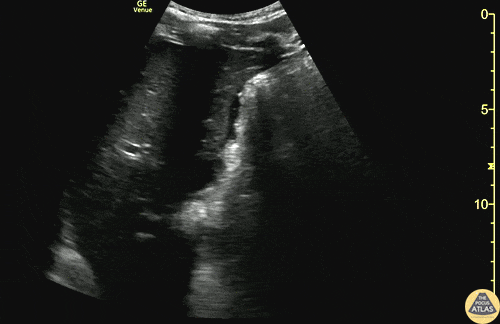

Trauma - Subtle +RUQ FAST from GSW

20s M presented as a walk in after sustaining a GSW to the hip. He was initially hemodynamically unstable, however responded well to transfusion of blood products and vitals normalized. FAST exam of the RUQ is shown here, with a trace amount of free fluid seen along the liver tip. FAST was also positive in the LUQ and pelvic views. Plain films demonstrated a retained missile in the abdomen. As he was hemodynamically stable, CT of the abdomen and pelvis was obtained, showing hemoperitoneum and free air concerning for bowel and vascular injury. The patient was taken emergently to the OR, where exploratory laparotomy demonstrated a pelvic hematoma and hemoperitoneum from an iliac vein injury, as well as multiple areas of small bowel injury. His injuries were repaired, he recovered well, and was discharged within days of his injury. Dr. Ian Eisenhauer, PGY1 Denver Health Residency in Emergency Medicine